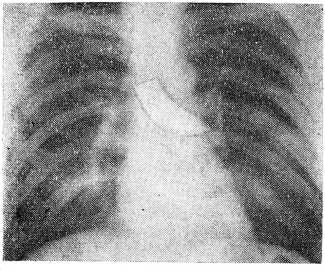

В результате просвечивания, рентгенографии и бронхографии, выполненных достаточно опытными специалистами, был установлен диагноз «инородное тело заднего средостения», в связи с чем больному и была назначена операция торакотомия. Между тем характерные анамнестические данные о выхождении воздуха из раны, наличие рубца на шее по ходу трахеи и само положение тени отломка ножа на обычных снимне в средостение, а через трахею в бронх (рис1).

Рис. 1. Отломок ножа располагается в проекции левого главного бронха.